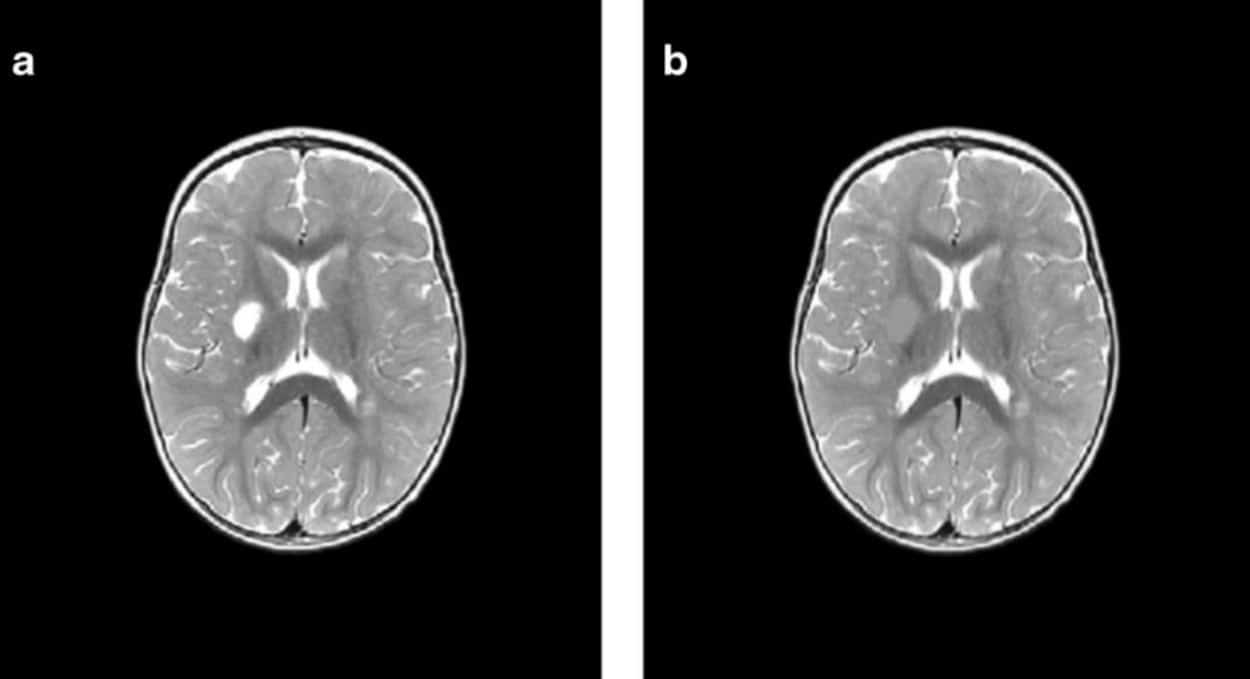

Исследователи проанализировали данные МРТ 35 детей, которые перенесли ишемический инсульт в возрасте до двух лет и лечились в больницах Екатеринбурга, Перми, Челябинска и Тюмени в период с 2015 по 2019 год. Возраст детей на момент инсульта варьировался от четырех дней до одного года 11 месяцев.

Для оценки последствий инсульта исследователи применили современный метод анализа снимков — воксель-базированную морфометрию. Упрощенно эту технологию можно представить так: на каждом МРТ-снимке слой за слоем вручную обводят контуры повреждений области мозга, а специальная компьютерная программа затем вычисляет точный объем этой зоны в кубических миллиметрах. Такая технология позволяет получить наиболее объективные данные по сравнению с традиционным МРТ-отчетом, направленным на определение качественных характеристик (точных границ инсульта, его локализации). Воксель-базированная морфометрия позволяет получить количественные данные: абсолютный и относительный объем поражения от общего объема мозга. Результат применения такого метода — точные числовые значения для последующего статистического анализа и сравнения.

Оказалось, что инсульты у младенцев и детей, достигших месячного возраста, различаются и по масштабам, и по характеру повреждений. Так, у малышей с перинатальным инсультом объем повреждения мозга оказался намного серьезнее, чем у старших: 7,9% против 1,6% от объема мозга. Также у новорожденных чаще встречались нарушения, затрагивающие кору мозга, смешанные и двусторонние инсульты, а у группы детей от 28 дней до двух лет преобладали локальные подкорковые очаги и повреждения только левого полушария.

Второй, менее очевидный вывод касался конкретных зон поражения. Выяснилось, что чаще всего удар у детей приходился на критически важные для развития лобную (68,6% случаев) и теменные (54,3%) доли. А именно эти зоны отвечают за движение, планирование, речь, мышление и восприятие пространства.

Но наиболее уязвимыми оказались зоны, снабжаемые кровью средней мозговой артерией, — 94,3% случаев. Почти у 63% детей была также повреждена внутренняя капсула, что часто ведет к когнитивным нарушениям, таким как невнимательность, апатия, абулия (безволие) и проблемы с памятью. В среднем объем поражения мозга составил примерно 20 тысяч кубических миллиметров — около 3,4% общего объема детского мозга.